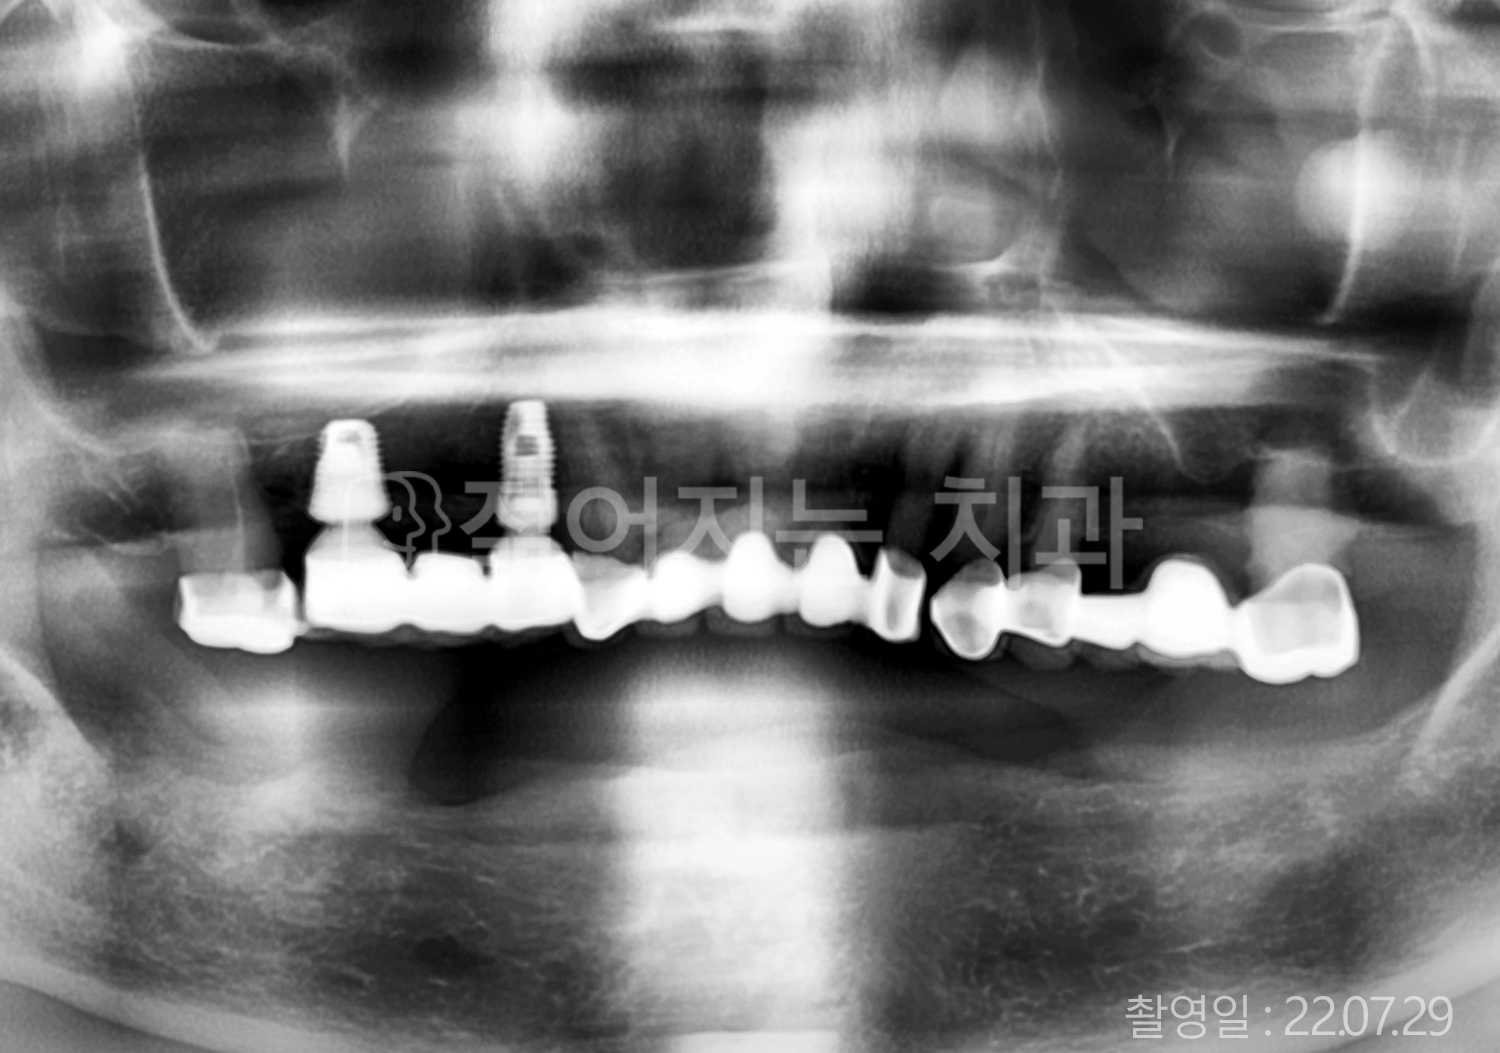

• 70대 고혈압, 고지혈증 전체치아 10개 이상 임플란트

• 60대 당뇨, 간염 전체치아 10개 이상 임플란트

• 80대 골다골증 전체치아 6개 이상 임플란트

• 70대 고혈압, 당뇨 전체치아 10개 이상 임플란트

• 60대 간 질환 전체치아 10개 이상 임플란트

• 60대 전체치아 10개 이상 임플란트

• 70대 전체치아 10개 이상 임플란트

• 50대 전체치아 10개 이상 임플란트

• 60대 고혈압, 고지혈증 전체치아 10개 이상 임플란트

• 40대 고지혈증, 뇌혈관 질환 전체치아 10개 이상 임플란트